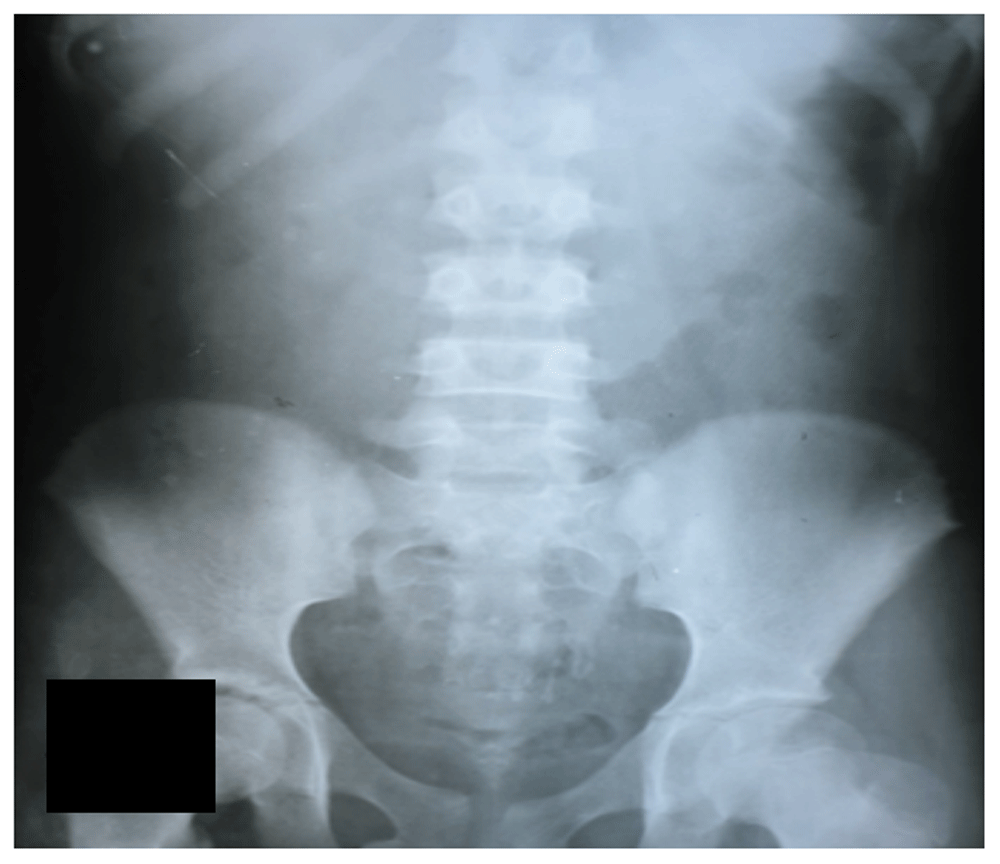

Two days later, the patient developed persistent vomiting along with constipation. She was taken to another local hospital where an X-ray of the abdomen was performed showing multiple air-fluid levels. The patient was restricted to oral intake both solids and liquids, an intravenous line was maintained, intravenous fluids and antibiotic ceftriaxone (2 gram once daily) were given, and a nasogastric tube was passed. Surgical opinion was sought at this time and surgical exploration was planned; however, this was refused by the family and the patient was taken to our hospital next day.

Figure 2. X-ray of the abdomen multiple air fluid levels.